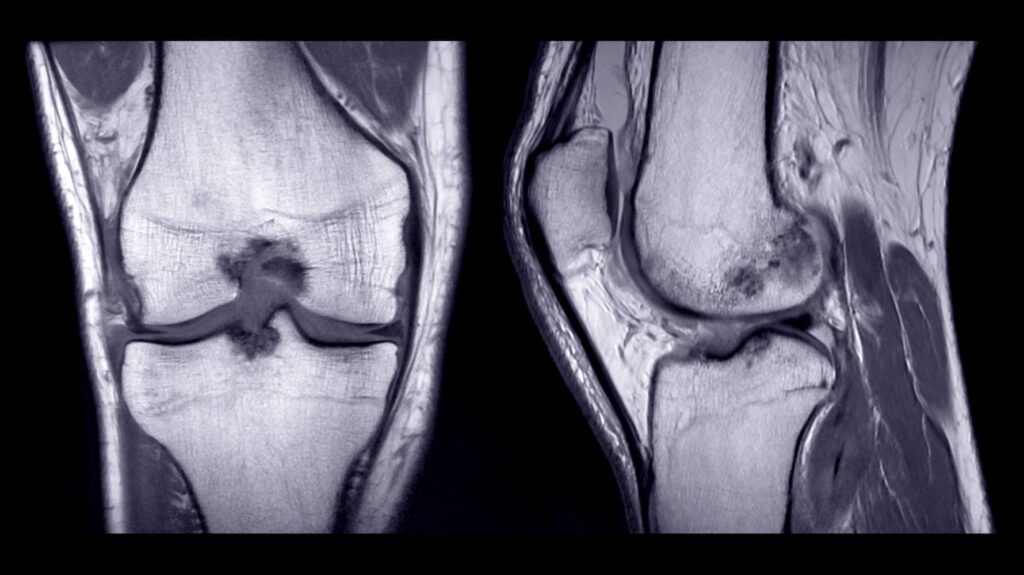

Bevor man sich in ärztliche Behandlung begibt, muss der Patient genau wissen, womit er es zu tun hat, damit die ihm zur Verfügung stehenden Möglichkeiten die effizientesten sind. In den meisten Fällen reicht eine körperliche Untersuchung aus, um das Vorliegen einer Patelladysplasie festzustellen. Bei der körperlichen Untersuchung überprüft der Arzt die Stabilität der Kniescheibe. Wenn die Kniescheibe sehr beweglich ist, leidet der Patient höchstwahrscheinlich an einer Patelladysplasie. Um mehr darüber herauszufinden, kann der Patient ein MRT-Knie machen lassen. Diese Art von Scan bietet mehr Informationen.

Patelladysplasie im MRT-Knie erkennen

Ein MRT des Knies liefert detaillierte Bilder der Knochen, Muskeln, Knorpel, Bänder, Sehnen und sogar einiger Blutgefäße. So kann der Arzt eine korrekte Diagnose stellen und die Behandlungsmöglichkeiten für den Patienten aufzeigen.